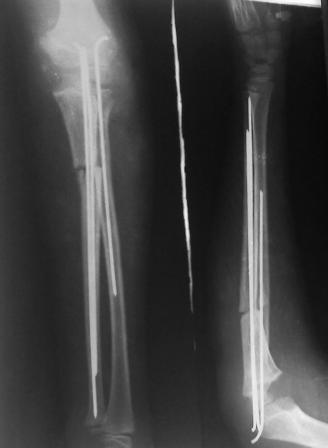

Многоуважаемые  коллеги,  всем  большое  спасибо!!!  Да,  здесь  было

повреждение  Монтеджиа, когда  нарисовал  скиаграмму все  стал

понятно. Мне  очень  понравились  рекомендации  Константина Требухина,

только  немножко  видоизменил; я  считал  так, если  деформацию

исправить то локт/кость должна  удлиниться, и  во вторых,  если  на

аппарате низвести  лучевую  кость,  то может наступить позиционное

несоответствие  в  дистальном  радиоульнарном  сочленение. 28.02.08г

операция- шарнирная  остеотомия  локтевой  кости на  уровне  деформации,

далее  вскрыт  плечелучевой  сустав, удалены  рубцовые тканы, после

исправления варусной  деформации  и  создания  физиологического  изгиба

локтевой  кости  головка луча  легко  вправилась, из  части  рубцовой

ткани  сделана  пластика кольцевндной  связки, трансартикулярная

фиксация  спицей, локтевая  кость  двумя  спицами.